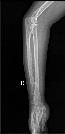

左侧股骨骨软骨瘤

病史: 入院情况:因“发现左股骨下段骨性包块5日”入院。查体:左股骨远端包块,大小约3.0cm×2.0cm×1.0cm,不规则,隆起,质硬。余无特殊。..

诊断与讨论: 左侧股骨骨软骨瘤。